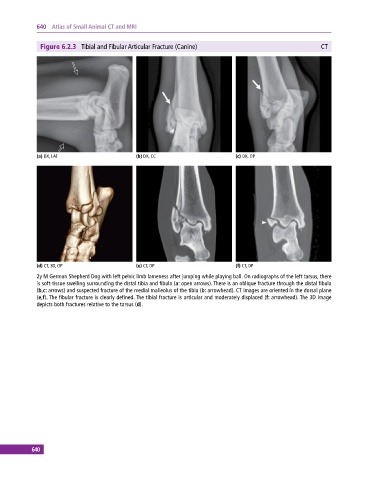

Figure 6.2.3 Tibial and Fibular Articular Fracture (Canine) CT

(a) DX, LAT (b) DX, CC (c) DX, OP

(d) CT, 3D, OP (e) CT, DP (f) CT, DP

2y M German Shepherd Dog with left pelvic limb lameness after jumping while playing ball. On radiographs of the left tarsus, there

is soft‐tissue swelling surrounding the distal tibia and fibula (a: open arrows). There is an oblique fracture through the distal fibula

(b,c: arrows) and suspected fracture of the medial malleolus of the tibia (b: arrowhead). CT images are oriented in the dorsal plane

(e,f). The fibular fracture is clearly defined. The tibial fracture is articular and moderately displaced (f: arrowhead). The 3D image

depicts both fractures relative to the tarsus (d).